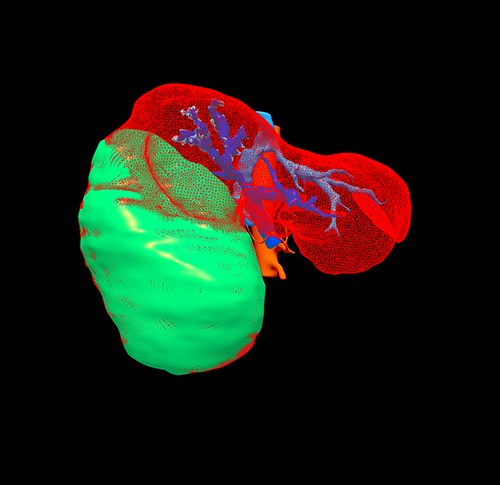

右肝巨大肝癌---右半肝切除